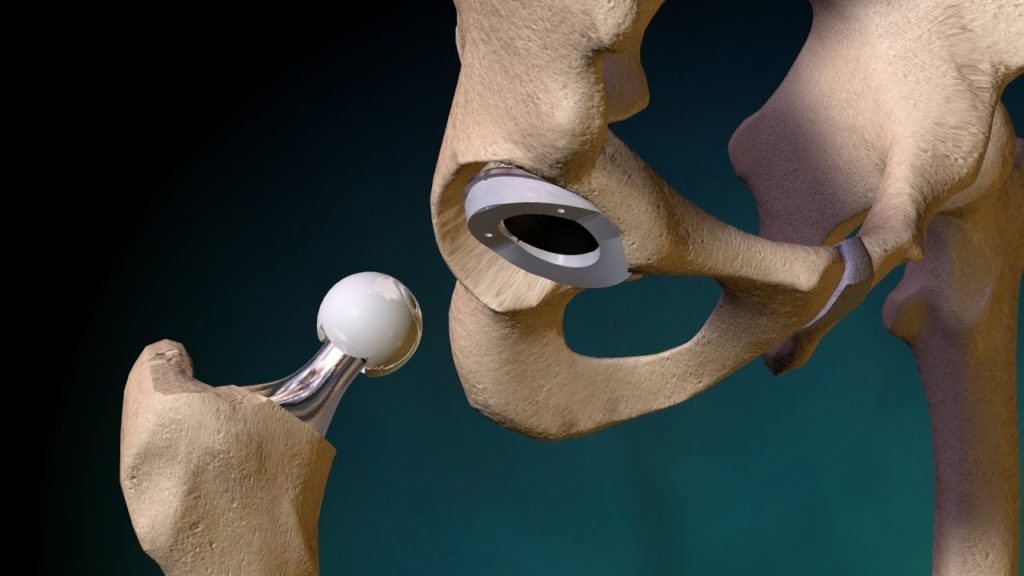

مفصل زلاق أحادي اللقمة

المفصل الزلاق أحادي اللقمة هو أسهل وأكثر صيغة شيوعاً من استبدال مفصل الركبة, في هذا السياق يتم تلبيس لقمة فخذ واحدة فقط بسطح معدني هذا المفصل يمكن الاستعانة به فقط في حال كانت جميع أجهزة الأربطة في الركبة سليمة وأن التلف يقتصر على اللقمة الخارجية أو الداخلية، بما يعني أن الغضروف فقط متآكل, كثير من المرضى ممن لديهم ركب فحجاء يظهرون هذا النوع من الضرر اعتماداً على الذي ينبغي استبداله، يتم وضع المفصل الزلاق داخليا أو خارجياً، على العكس في الجانب المقابل من مفصل الركبة حيث يتم تلبيس قاعدة معدنية، والتي تحتوي على مجسم من اللدائن يمكن أن ينزلق عليه المفصل الصناعي.

هذا النوع من الأعضاء البديلة هو أكثر طرف بديل للركبة شيوعاً ويستبدل مفصل الركبة بشكل كامل: يتم استبدال سطوح المفصل الخاصة بعظم الفخذ وعظم الظنبوب وأحيانا الرضفة المهم في هذا السياق أن تكون أربطة الركبة المثبتة للمحور كالرباط الخارجي والداخلي محافظ عليها و فعالة بهذا يمكن للمرء أن يزرع هذا العضو البديل حتى لو كان الرباط الصليبي الأمامي مدمر الأربطة الخارجية والداخلية تساهم بشكل حاسم في توازن الركبة حينما يكونان الرباط الصليبي الأمامي والخلفي غير ثابتين يمكن زراعة عضو بديل خلفي مثبِّت هذا العضو يتبنى وظائف الرباط الصليبي من خلال تحويل ضغط الفخذ للخلف والظنبوب للأمام عمليات الركبة الصناعية.